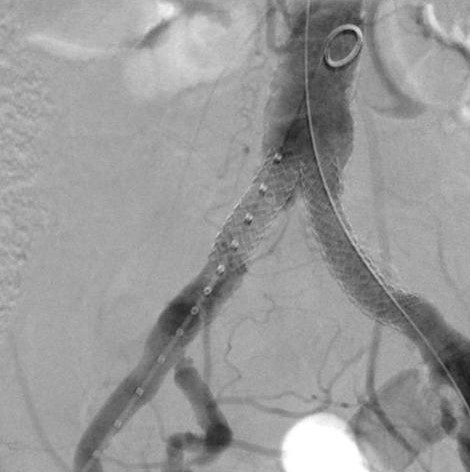

Widely patent arteries demonstrating VBX Stent Graft flexibility and radial strength in a highly tortuous vessel